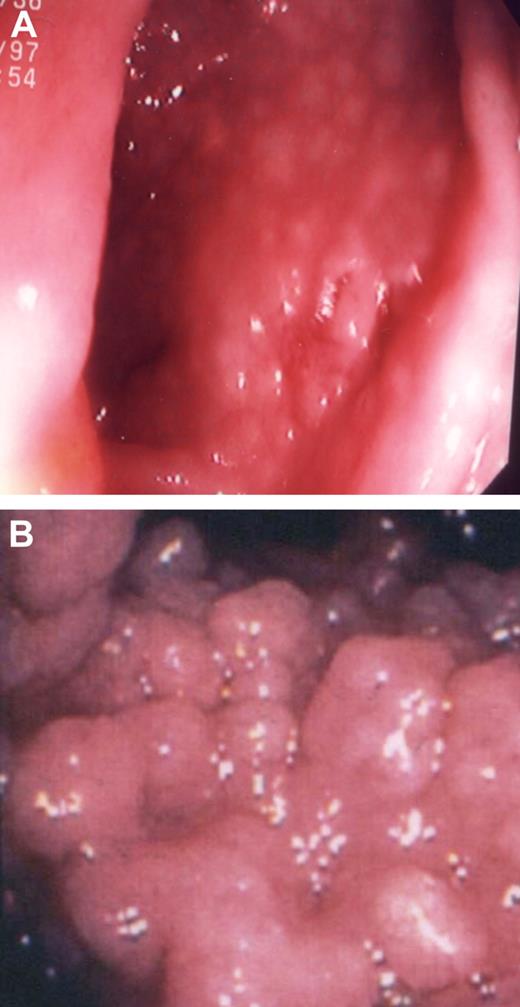

On biopsy, the gastrointestinal mucosa contains excess intraepithelial lymphocytes, villous blunting, lymphoid aggregates, granulomas, crypt distortion, and as noted previously, a characteristic lack of plasma cells.64,65 Another common feature is villous flattening in the small intestine suggesting celiac sprue. However, we have not found wheat withdrawal to be beneficial, and instead it leads to additional weight loss. In the worst cases, significant loss of essential nutrients (eg, calcium, zinc, and vitamins A, E, and D) leads to bone loss and neurologic deficits, which are not easily reversed.67 Nodular lymphoid hyperplasia (containing an expanded number of B cells but no plasma cells) is common and may be observed on endoscopy in any area of the gastrointestinal tract; when massive, this can lead to both severe chronic diarrhea and weight loss (Figure 2). Initial treatment is determined on the basis of culture results, biopsy findings, and usually includes antibiotics, restoration of nutrients, and rehydration.

Gastrointestinal lymphoid nodules. (A) A 50-year-old woman who had a history of a duodenal ulcer, now resolved. She had a repeat gastroscopy for symptoms of gastritis; H pylori was not found. The mucosa of the stomach folds of this female patient contained numerous lymphoid follicles. (B) The jejunum of a 28-year-old male patient containing massive nodules of lymphoid hyperplasia; he had experienced a 20-lb weight loss.